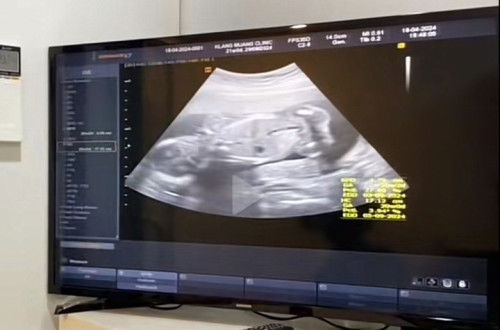

ซาวด์ดูเพศ ฉีดวัคซีนไข้หวัดใหญ่ 16วีค

วันนี้คุณหมอนัดตรวจ 16วีค ซาวด์เพศฉีดยาไข้หวัดใหญ่ คุณหมอบอกว่าหนูมีกรีบตรงกลางนะครับ คุณแม่ได้ลูกสาวนะ อาการทั่วไปคือแพ้ท้องนิดหน่อย เพลียหนักง่วงมาก แต่ตอนนี้อาการแพ้เบาแล้วค่ะ อาหารโปรดคือเมนูเส้นทุกอย่าง ไม่ชอบกินของหวาน สิวไม่ขึ้นรักแร้ไม่ดำ ท้องมองดูกลมๆ ค่ะ #ทีมลูกสาว #ทีมสิงหา #ทีมมังกรทอง